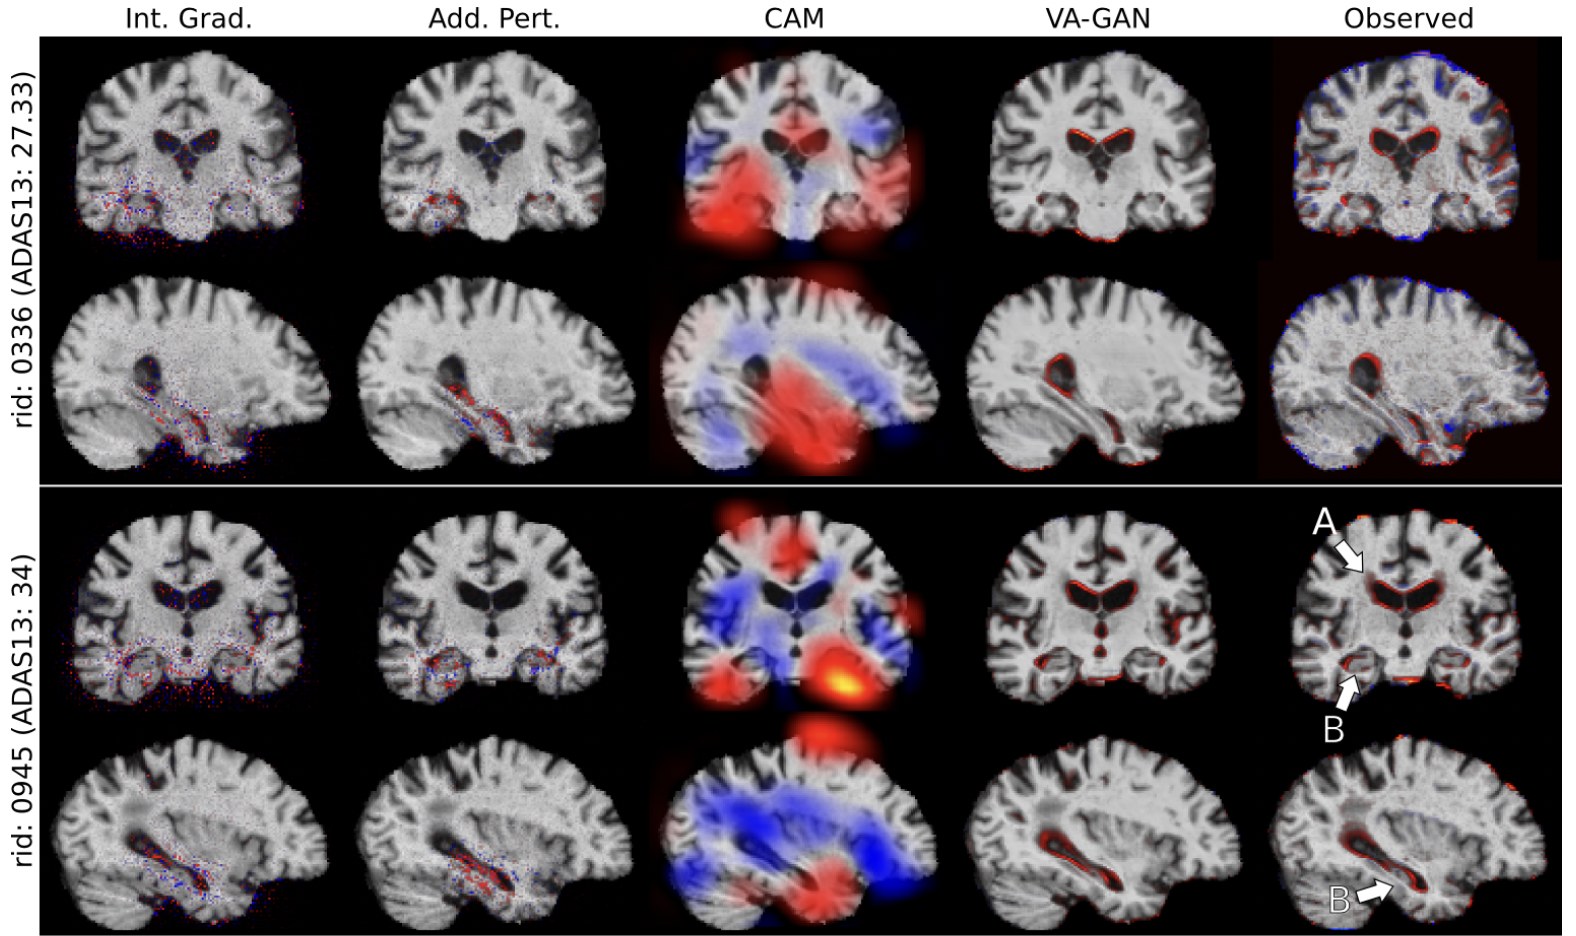

The rapid developments and early successes of deep learning technology in medical image analysis (and other fields) have caused the field to prioritize predictive accuracy over human integration. However, it is becoming increasingly clear that black box models are unlikely to find clinical acceptance, can lead to ethical problems when neither the patient nor the doctor understand the reasoning behind a prediction, and are difficult to certify. Our research goals in this branch are to develop adequate explanations for predictions of deep learning models, and perhaps more importantly, to build inherently interpretable models rooted in prior clinical knowledge.